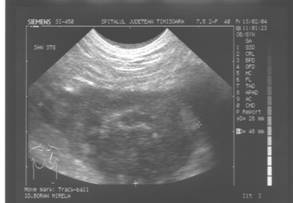

MASTOZA FIBROCHISTICA

Tumorile si pseudotumorile sanului sunt patologii frecvente, dominate mai ales de fibroadenom, care este o patologie obisnuita la femeie tanara.

Anumite patologii pot avea un aspect ingrijorator (adenoza sclerozanta, CSN, CPA) care trebuie sa determine continuarea explorarilor.